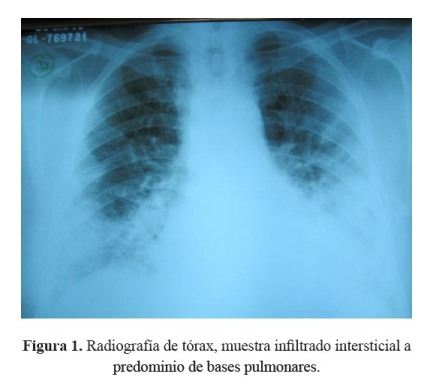

La radiografía de tórax mostró infiltrados intersticiales predominantemente en bases pulmonares ( Figura 1).

El paciente tenía antecedente de insuficiencia cardíaca y de fibrilación auricular paroxística por lo que recibía tratamiento con amiodarona, acudió con una historia de 3 semanas de tos, disnea y fiebre, llamando la atención desde el ingreso la radiografía de tórax con infiltrado bibasal tipo consolidado pero también con compromiso intersticial en la periferia. Recibió tratamiento para neumonía adquirida en la comunidad con ceftriaxona y claritromicina, además diuréticos por el antecedente de insuficiencia cardíaca. La evolución fue estacionaria, se cambió la cobertura antibiótica a ceftazidima y amikacina; sin embargo, la fiebre persistió. La tomografía de tórax confirmó lo que se evidenciaba en la radiografía, un compromiso intersticial difuso, con áreas de patrón en vidrio esmerilado en la periferie y patrón en panal de abeja en bases.